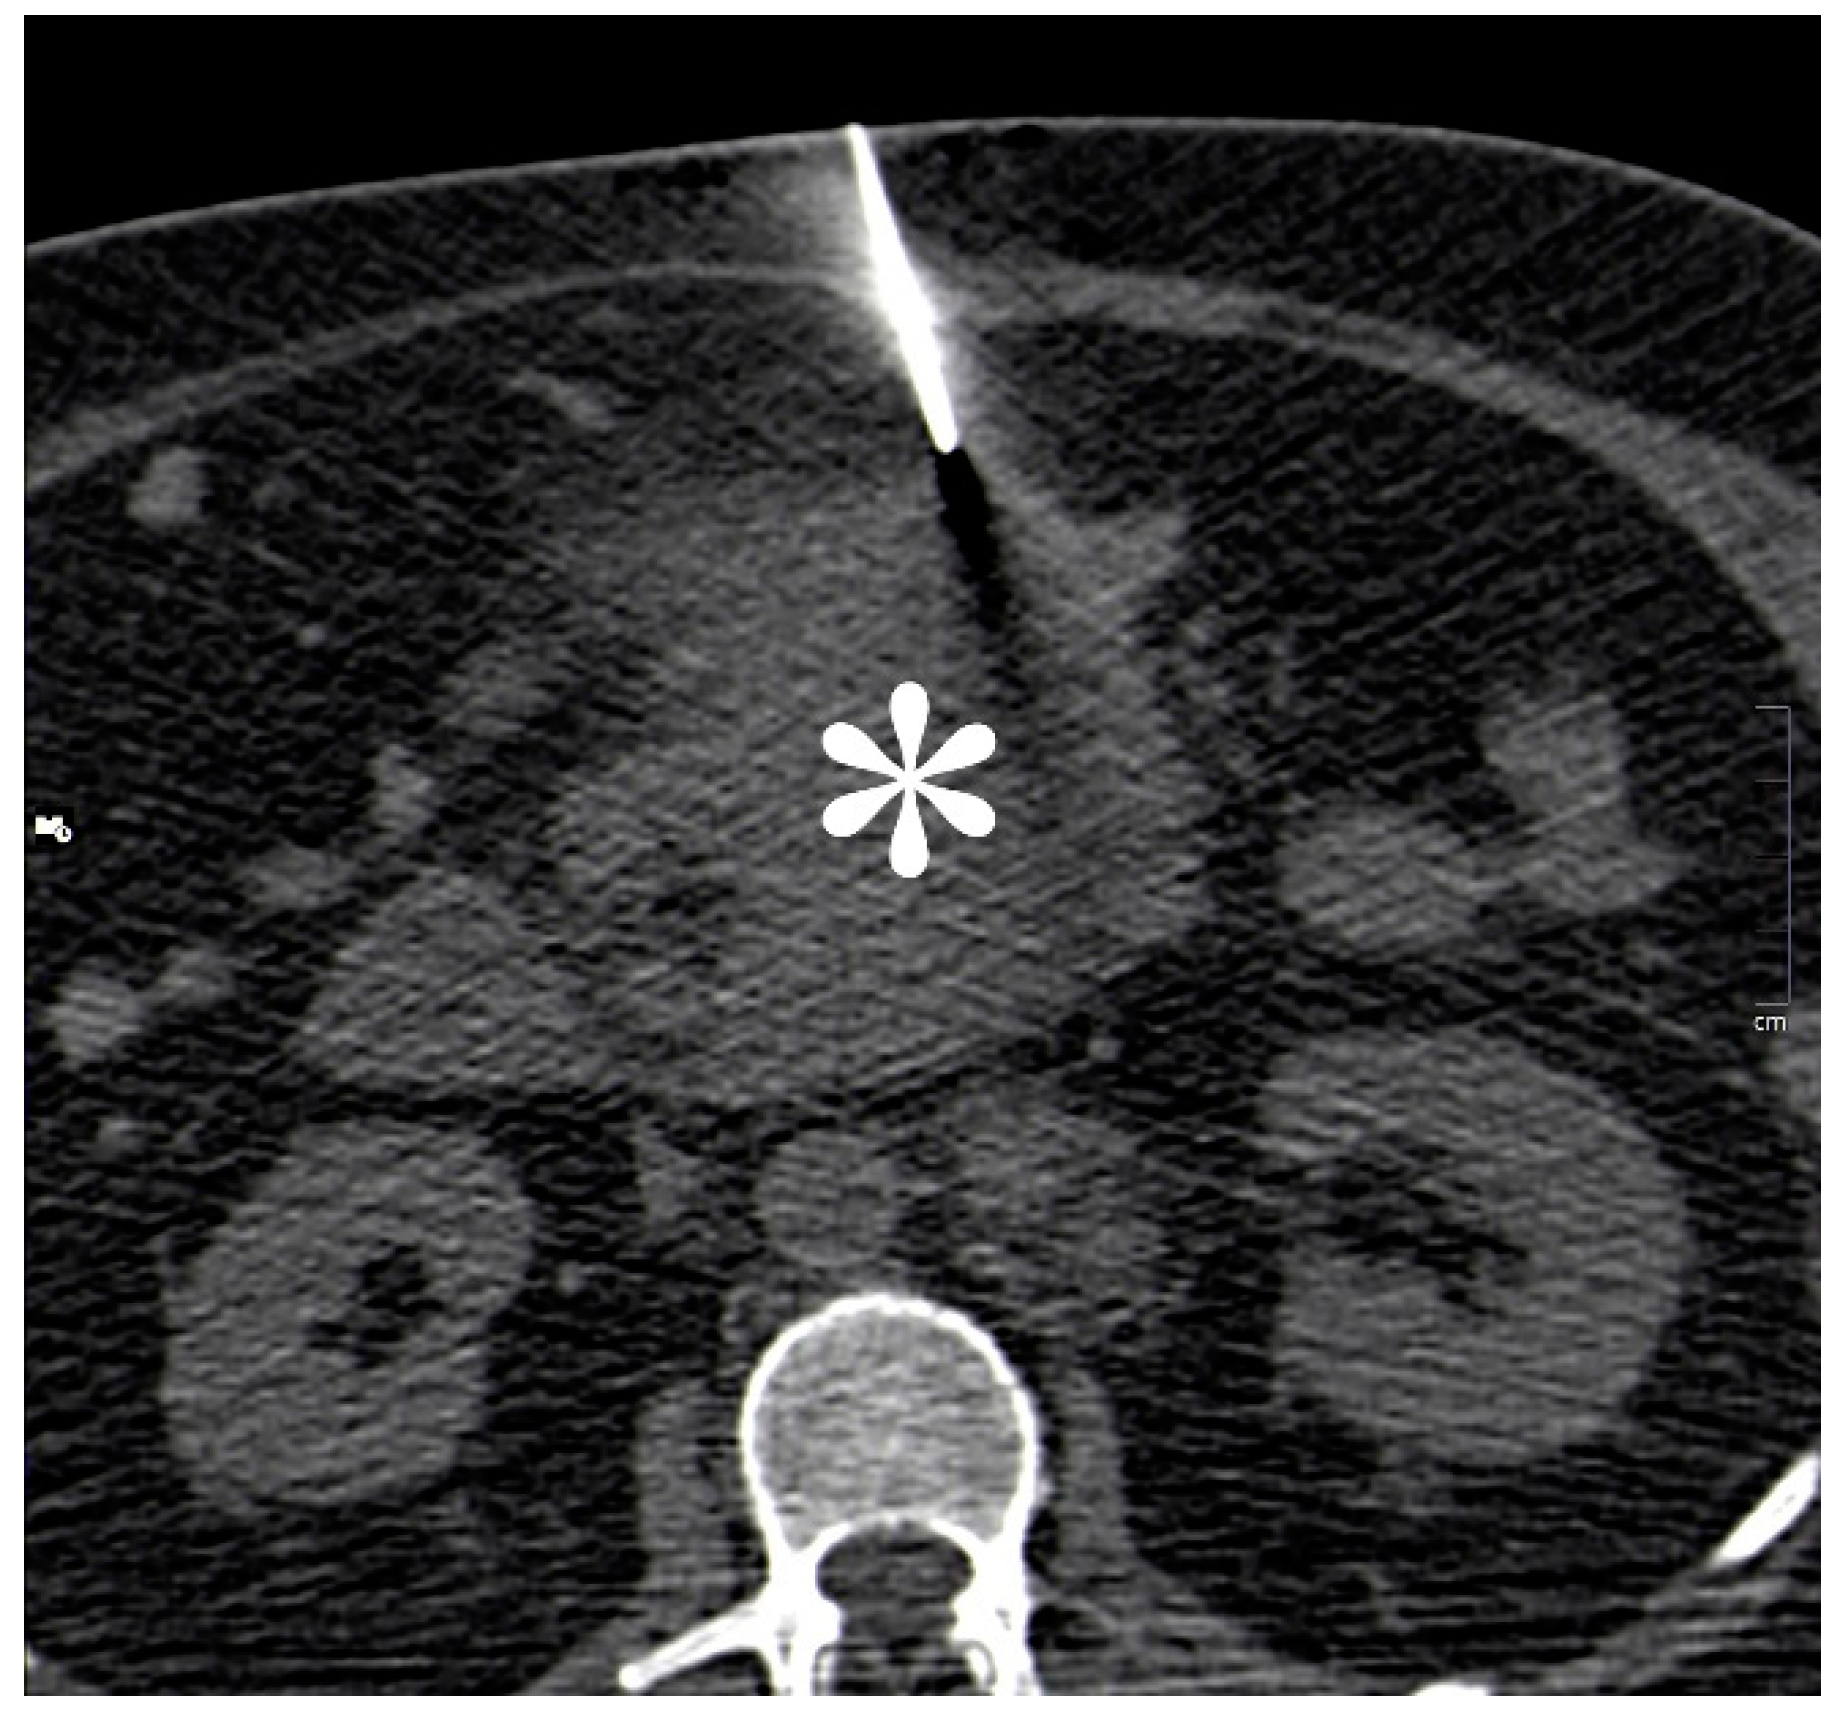

CT guided biopsy of the mesenteric mass (Figure 3) was performed to obtain a histological diagnosis. The analysis of this, demonstrated extensive infiltration of the tissue by immature blasts, with destruction of the native architecture (Figure 4 and Figure 5). Immunohistochemistry with myeloperoxidase immunostain (Figure 6) confirmed the myeloid lineage of these blasts, which had CD34− and CD117+, MPO+, PU+ and CD7− phenotype.

Figure 3.

Unenhanced CT image from CT guided biopsy procedure showing a 15 G coaxial introducer at the edge of the mass (white asterisk) through which two 16 G × 2 cm (Achieve®, CareFusion; San Diego, CA, USA) cores of tissue were obtained.